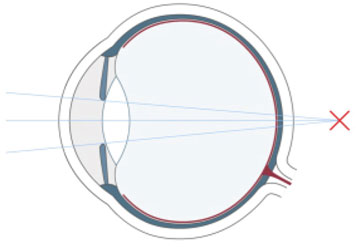

Wer unscharf sieht, war bisher gezwungen, sich mit Brillen und Kontaktlinsen zu behelfen. Die Refraktive Chirurgie ist mit dem LASIK-Verfahren in der Lage, die Sehschwäche am Auge selbst zu korrigieren. Das LASIK-Verfahren hat sich als die erfolgreichste und weltweit am häufigsten angewandte Methode zum Augenlasern etabliert.

Bei Kurzsichtigkeit, Weitsichtigkeit und Alterssichtigkeit sowie bei einer Hornhautverkrümmung setzen wir einen Augenlaser ein, der sich auf dem allerneuesten Stand der Technik befindet. Das Augenlasern führen wir ambulant durch, der Eingriff selbst dauert nur wenige Minuten. Welche Methode beim Augenlasern zum Einsatz kommt, wie sich der Ablauf beim genau gestaltet und welche Kosten hierdurch entstehen, ist abhängig von der vorliegenden Fehlsichtigkeit.